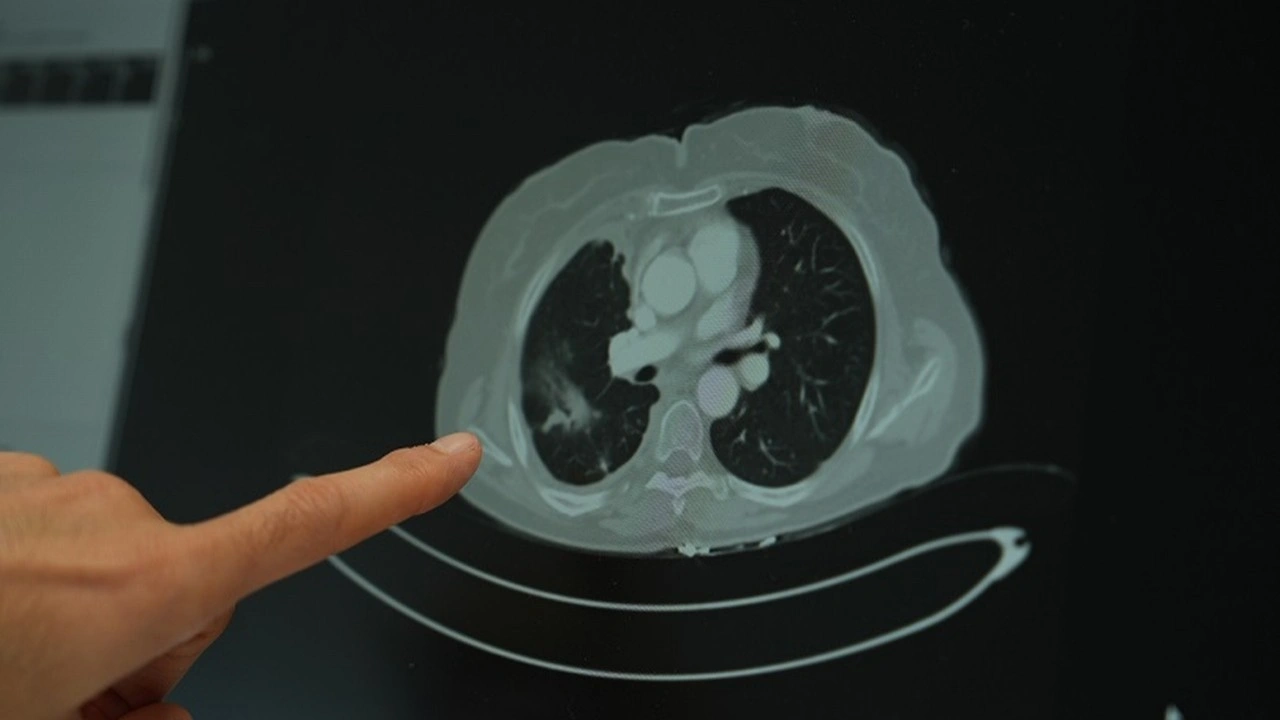

Sigara kullanımının akciÄŸer kanseri üzerindeki etkisini deÄŸerlendiren Doç. Dr. ÅžimÅŸek, uzun süre sigara kullanan kiÅŸilerde düşük doz radyasyonla yapılan tomografi taramalarının önerildiÄŸini belirterek “Sigara içen bireylerde akciÄŸer kanseri riski yüksek. Bu nedenle düşük doz radyasyonlu taramalar, erken tanı açısından önemli” ifadelerini kullandı.